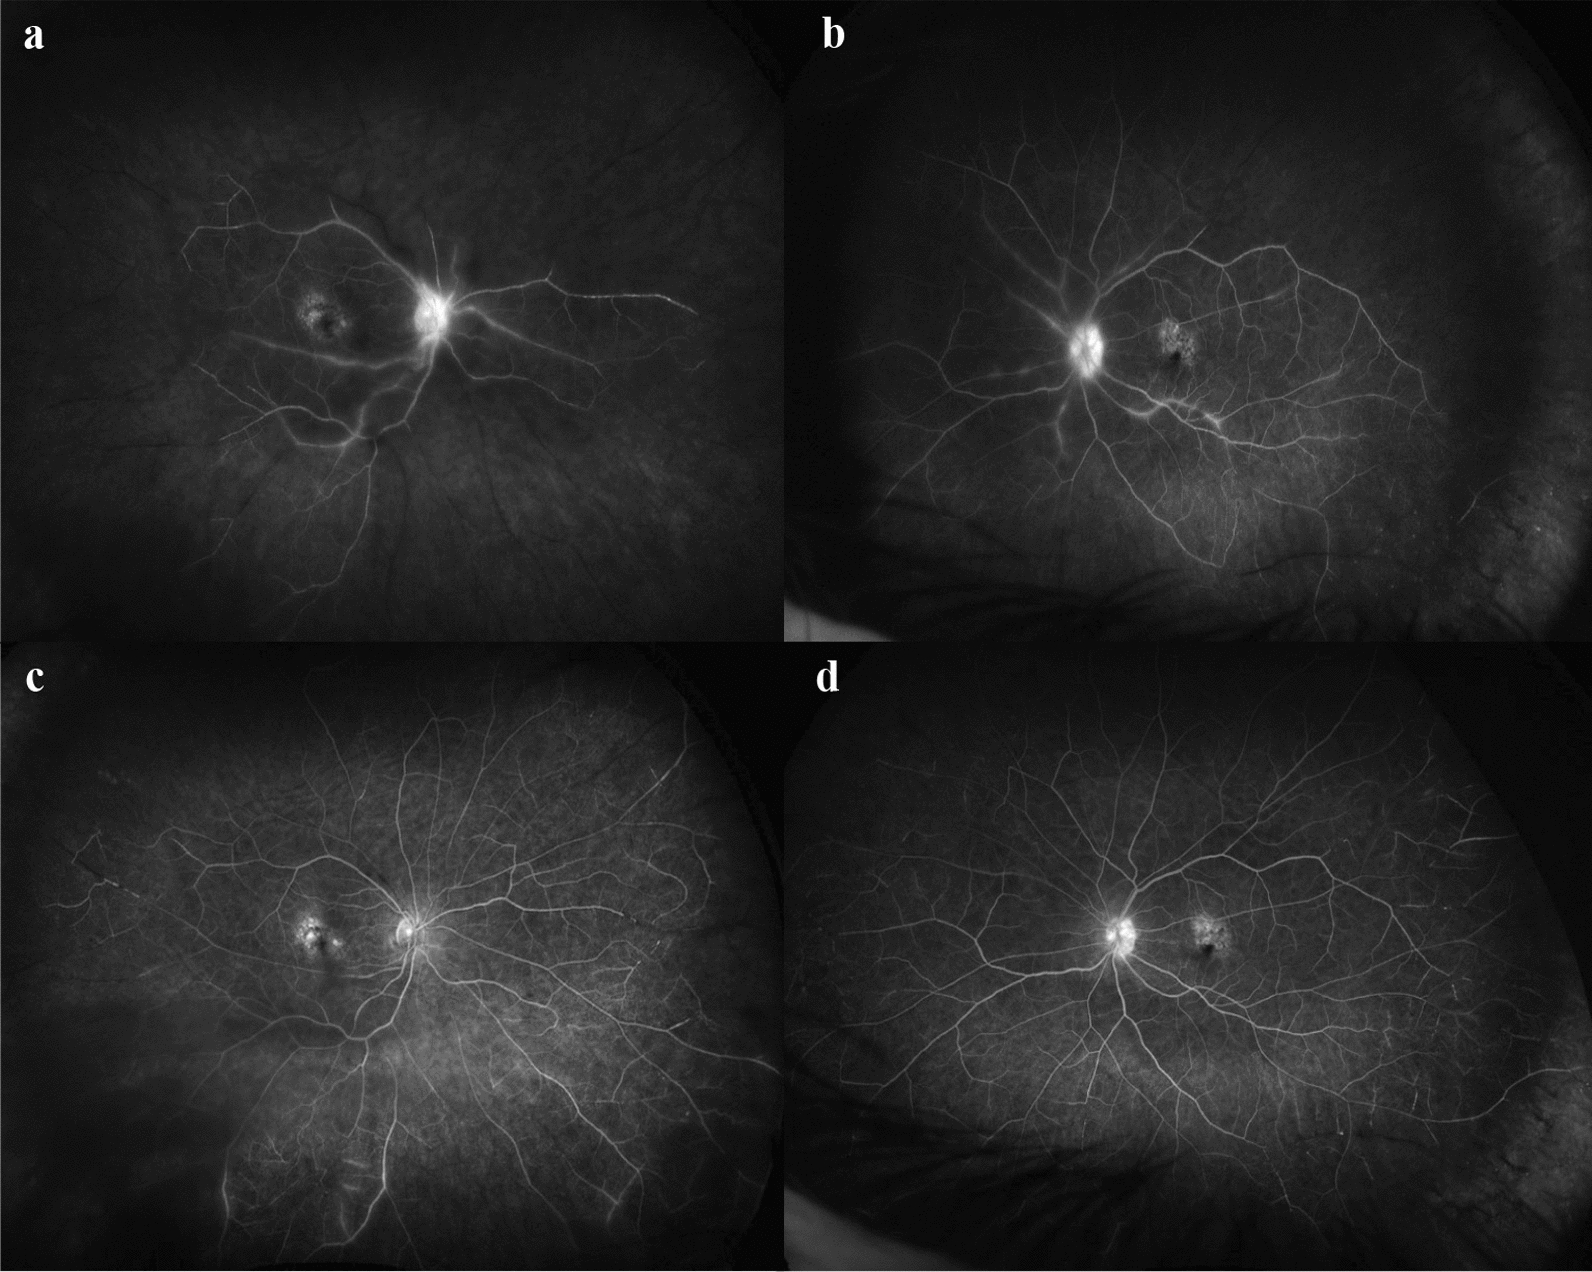

Case presentation: A 72-year-old female with age-related macular degeneration presented with bilateral retinal occlusive vasculitis following intravitreal faricimab injections. The patient was treated with 3 days of intravenous methylprednisolone followed by oral prednisolone taper and topical steroid therapy. Resolution of retinal occlusive vasculitis was observed 2 months post treatment.